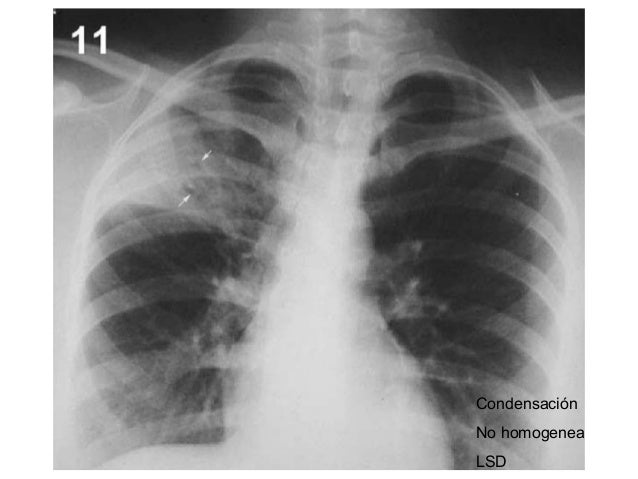

Mujer de 80 años con importante fibrosis pulmonar en rx de tórax el electrocardiograma con importante crecimiento y sibrecarga del ventrículo derecho por. La fibrosis pulmonar puede deberse a la exposición a distintas sustancias y también puede ser secundaria a otras enfermedades. La fibrosis pulmonar idiopática (fpi), la forma más común de neumonía intersticial idiopática, causa fibrosis pulmonar progresiva. Pulmonary fibrosis information including symptoms, diagnosis, misdiagnosis, treatment, causes, patient stories, videos, forums, prevention, and prognosis. Lung scars can result from illness or medical treatment, and they are permanent. Familial pulmonary fibrosis for patients. La fibrosis pulmonar es una forma de enfermedad pulmonar intersticial. It can occur in a wide range of clinical settings and can be precipitated by a multitude of causes. Find the most popular drugs, view ratings and user reviews. Hospital de la santa creu i sant pau. Medical marijuana can help relieve pulmonary fibrosis symptoms. Las enfermedades pulmonares intersticiales son un grupo de hay muchos tipos diferentes de fibrosis pulmonar. You may have pulmonary fibrosis for some time without any symptoms.